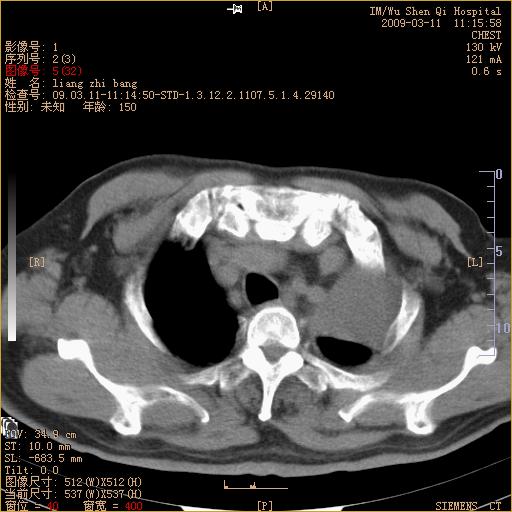

标题: CT18604:男,60岁,咳嗽一月余 [打印本页]

标题: CT18604:男,60岁,咳嗽一月余

1)考虑左肺上叶中央型肺癌并左肺上叶肺不张;建议必要时行纤支镜检查进一步明确诊断。2)左侧胸腔积液。

肺门肿块、支气管开口闭塞伴肺不张及胸水!典型的中心型肺癌变现!

1、左肺上叶中央型肺癌并上叶阻塞性肺不张。

2、左侧胸腔少量积液,右侧胸膜轻度增厚。